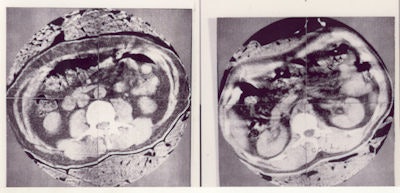

Actually the first body scan was performed on a very thin engineer, Tony Williams, who could fit into the head scanner. The initial images on the Emerald body scanner were of Hounsfield himself, and reputedly he recognized in the images his lunch of crisps and beer eaten at the Blue Anchor pub! The EMI team presented the body images at the Computed Cranial Tomography International Symposium and Course held in Bermuda in March 1975. When Hounsfield showed the image of his abdomen, the audience let out a gasp, followed by a standing ovation. By October 1975, there were EMI Emerald body scanners at Northwick Park Hospital, the Mallinckrodt Institute of Radiology, and the Mayo Clinic. The production model was marketed as the CT5000.